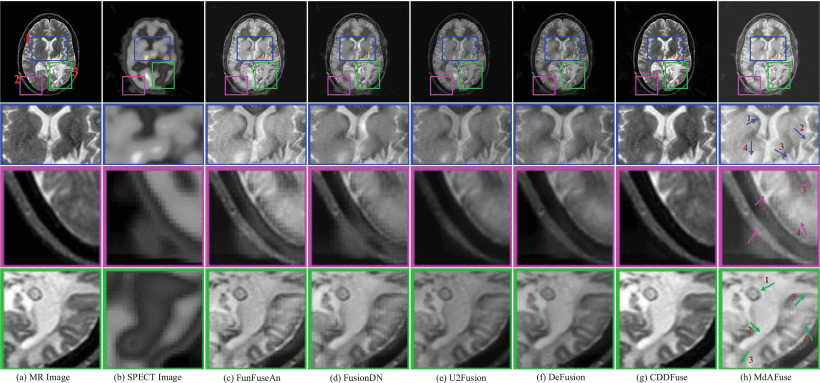

Subsequently, experiments were conducted on several kinds of DL-based image fusion methods and their fusion results were copared agaisnt MdAFuse model. As illustrated in the figure below, the first and second columns show the MR and SPECT source images to be fused, and the following six columns show the fusion results obtained by six kinds of fusion methods, including MdAFuse. From these results, we can observe the differences among different fusion methods. Overall, it can be observed that the fusion images generated by U2Fusion and CDDFused seem not to consider the information of SPECT. While FusionDN and DeFusion methods preserve SPECT information in the fusion images, some loss of information can still be observed. The image fusion results from the FunFuseAn method are relatively better, showing visual similarity to MdAFuse in this paper. Therefore, we enlarged three small areas to further compare and analyze. In the first line, we use three colors to mark three different areas and enlarge them, as shown in the second to fourth lines.

Performance Comparisons: The quality of our MdAFuse method is comparable to those of existing DL-based methods. From (c) to (h) are FunFuseAn [Ext. Ref.], FusionDN [Ext. Ref.], U2Fusion [Ext. Ref.], DeFusion [Ext. Ref.], CDDFuse [Ext. Ref.] and MdAFuse (dataset No. 029)